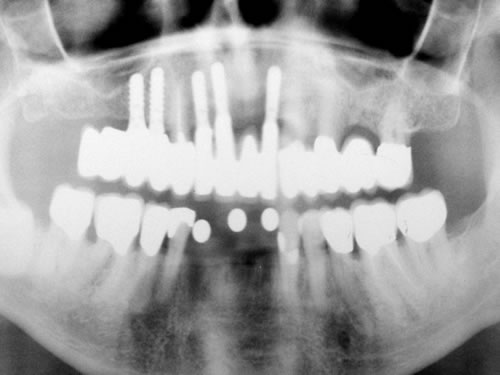

Für den Oberkiefer ist eine CT-Untersuchung notwendig, die ebenfalls mit einer Schablone durchgeführt wird. Auswertung, Planung und Implantations-Simulationen ergeben, dass sechs Implantate im vorderen Kieferabschnitt verankert werden können. Auch die Qualität des Knochens lässt eine Einpflanzung ohne weitere Maßnahmen zu. Diese Behandlung soll nach der Versorgung des Unterkiefers erfolgen.